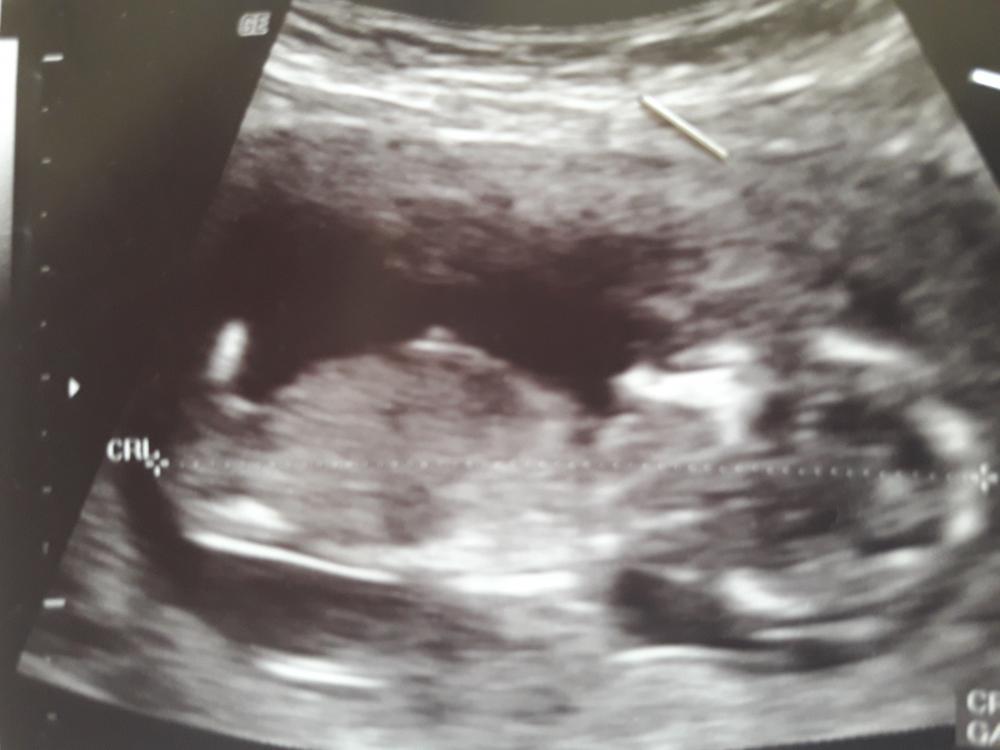

بنات انا من تجمع الاشبال الله يرزقكم بالبنوتات ....في عضوتين قالولي انه بنت ... يبين الجنس من هالصورة فرحوني الله يفرحكم انا بلاسبوع 13 و3ايام

مررره بدري ياعسل وحتى الخطأ وارد بهالوقت .. اصبري وسويه الأسبوع 16 وبيكون مره مبين اذا ولد او لا .. لأن اولادي اسويه عالأسبوع 16 يكون العضو جداً واضح ولدي الأخير كنت ابي بنت والدكتوره ماتكلمت بس لفتلي الشاشه وشفته بعيني واضح لذلك لاتعتمدين كلام أحد روقي لين نهاية الرابع وروحي والله يرزقك بالولد الصالح يارب